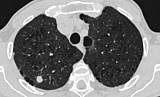

Чтобы уточнить диагноз, пациенту провели необходимые исследования, включая компьютерную томографию лёгких, бронхоскопию и современный тест на туберкулёз — ТиграТест. По итогам обследования медики приняли решение о хирургическом удалении небольшого участка лёгкого.

По результатам гистологического исследования мужчине был поставлен диагноз «туберкулез лёгких». Ему назначили лечение, пояснили в Министерстве здравоохранения Алтайского края.